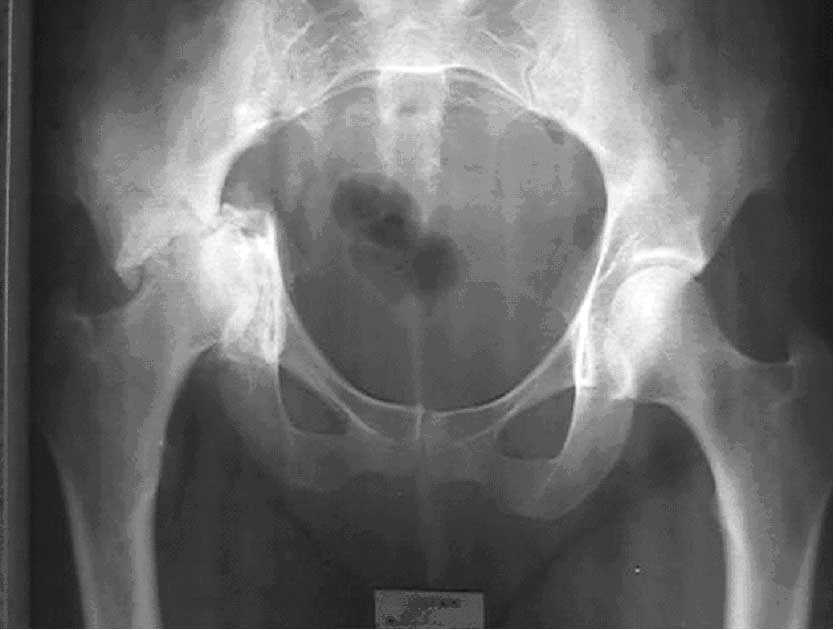

Больная 48 лет. С 1994 года болеет лимфогранулематозом. В 1994 и 1995 годах приняла лучевую терапию. С 2000 года беспокоят прогрессирующие боли в правом тазобедренном суставе и хромота. В настоящее время по заключению гематолога в лечении не нуждается.Диагноз: патологический поперечный перелом вертлужной впадины.Предполагается тотальное эндопротезирование.Вопрос: предложения по тактике операции ?

По моему решение об эндопротезировании здесь правильное. Необходимо призвести остеосинтез тазового кольца иначе не удастся закрепить

ацетабулярный компонент. В этом случае я бы исползовал костную пластику дна впадины костными чипсами в сочетании с гидроксиаппатитом ( или без него) и остеосинтез антипротрузионным кольцом типа Буршнайдера, Ганса, G.A.P. или

реконструктивным тазовым кольцом Link (в зависимости от того, что сможете найти. С последующей установкой цементной чашки.

К сожалению, ситуация с которй Вы встретились не благоприятная. На мой взгляд, целесообразно протезировать с использованием кольца Burсh-Schnaider'a и аутокостной пластикой дна вертлужной впадины. Проблемы будут с фиксацией кольца, т.к. имеется линия остеолиза или перелома) подвздошной кости. Винты нужно

проводить очень осмотрительно. Полиэтиленовый вкладыш лучше устанавливать на цемент с гентамицином. Все остальное - как обычно.